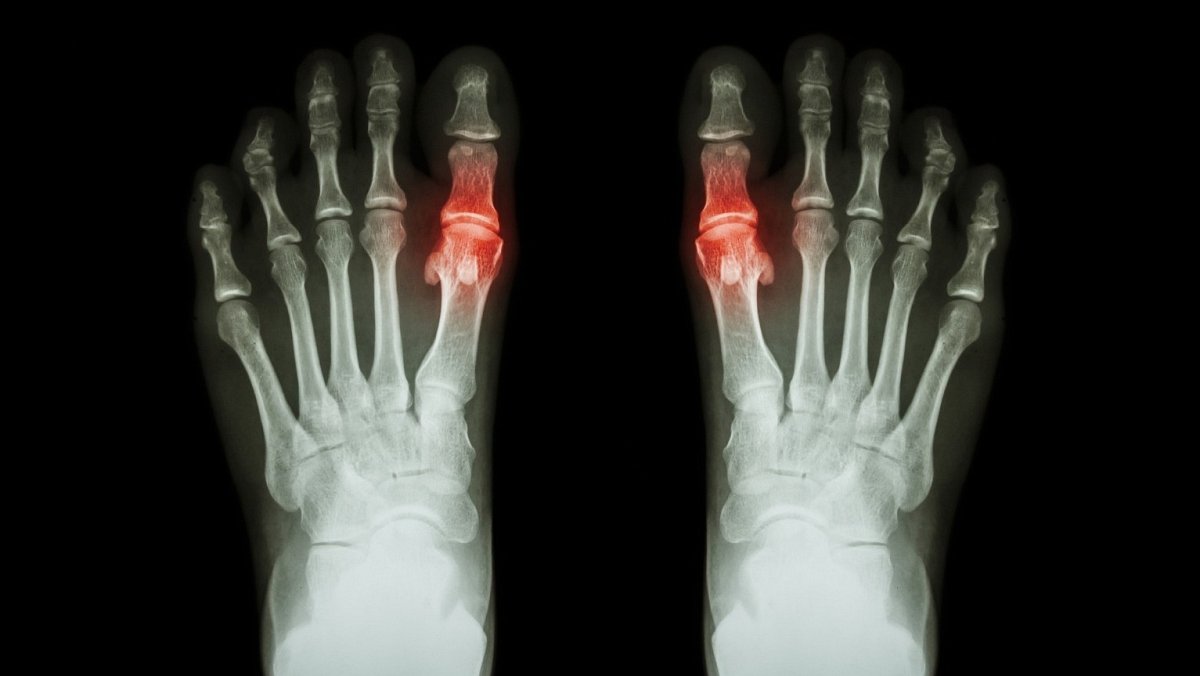

Dna, jinak také pakostnice, je revmatologické zánětlivé onemocnění, jehož projevy se mohou objevovat při dlouhodobě vysokém přísunu purinů do těla. Jedná se o látky, které jsou obsaženy hlavně ve stravě bohaté na bílkoviny. Tato choroba, dříve také nazývaná „nemoc králů“ nebo „nemoc bohatých“, se projevuje v návaznosti na tzv. hyperurikemii, což je zvýšená hladina kyseliny močové. Ta může být způsobena zvýšenou produkcí kyseliny močové při maligních onemocněních, nedostatečným vylučováním v důsledku poklesu ledvinných funkcí, nadměrnou konzumací alkoholu a nápojů slazených fruktózou. Zvýšená hladina kyseliny močové v krvi zpravidla vede k ukládání krystalů její soli do šlach, kloubů (dnavá artritida) a ledvin (dnavá nefropatie). Ty poté mohou vyvolat silně bolestivé zarudnutí, které může přejít do akutního dnavého záchvatu.

Pakostnice nejčastěji postihuje palec u nohy. „Postižené místo bývá horké, oteklé, velmi zarudlé a bolestivé. Kůže bývá napjatá a lesklá, čemuž se říká „fenomén zrcátka“. Nástup dnavého záchvatu může být doprovázen horečkou a dochází k němu nejčastěji v noci nebo časných ranních hodinách. Může trvat několik hodin nebo několik týdnů, obvykle trvá 7–14 dnů. Bolest i otok poté sice ustoupí, ale samotná nemoc v těle zůstává. Dnavý záchvat může proběhnout pouze jednou za život, ale také se může v budoucnu opakovat,” uvádí odborná konzultantka BENU lékáren, PharmDr. Ivana Lánová.